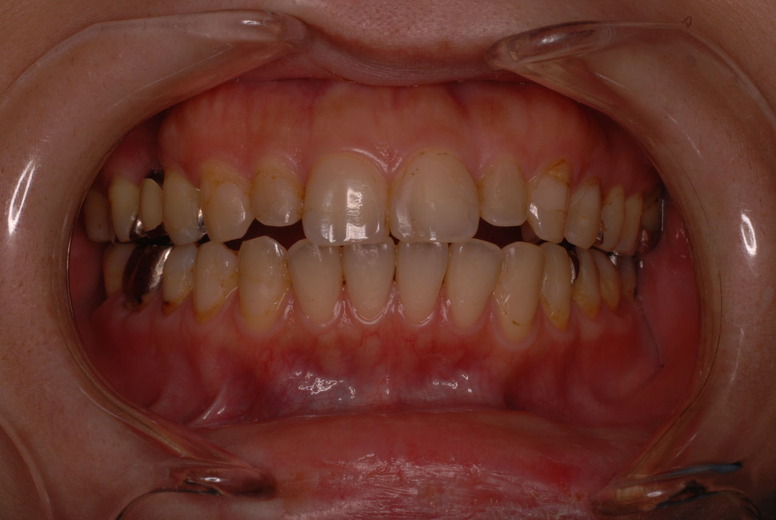

親知らずを取ることを嫌がる方が多いのですが、もし親知らずとその隣の14歳大臼歯の間に虫歯ができたり歯周病を罹患した場合、どれほど治療が大変で再発も起こりやすいか理解できない方がおおいのです。